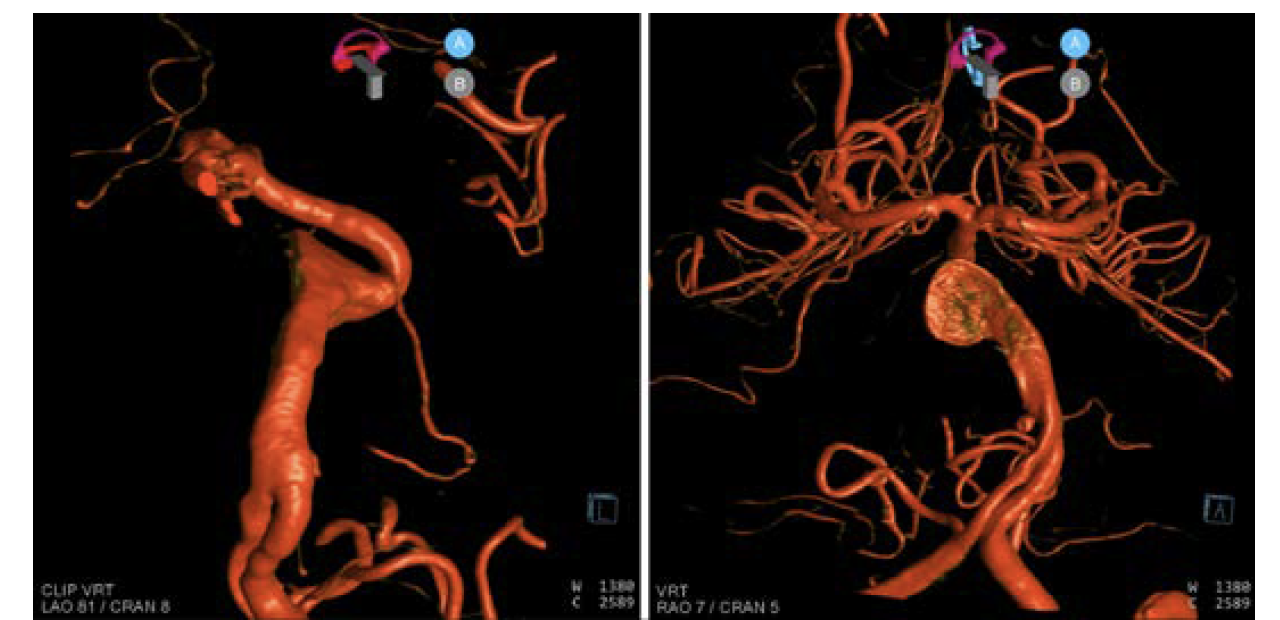

In the first case, a healthy 59-year-old patient presented to the ER with aneurysmal subarachnoid hemorrhage and an unusual ruptured right internal carotid artery dorsal wall aneurysm (Figure 6). While each practice approaches these somewhat differently, this is a flow diversion case for Goodman Campbell Brain and Spine.

The patient returned for a 6-month follow-up angiography (Figure 9). 3D DSA and DynaCT Micro fusion imaging demonstrated the stent construct and aneurysm segment. The aneurysm was cured, and the patient was neurologically normal and returned to work.

In this case, a healthy 62-year-old presented with a partially thrombosed giant vertebrobasilar junction and midbasilar aneurysm (Figure 10).

The patient returned for a 6-month follow-up angiography. Anterior-posterior, lateral, and 3D dual volume imaging was done at 6 months (Figure 18). Note the calcified shell of the aneurysm on the 3D image. The patient was neurologically normal and returned to work as well as running multiple times per week.